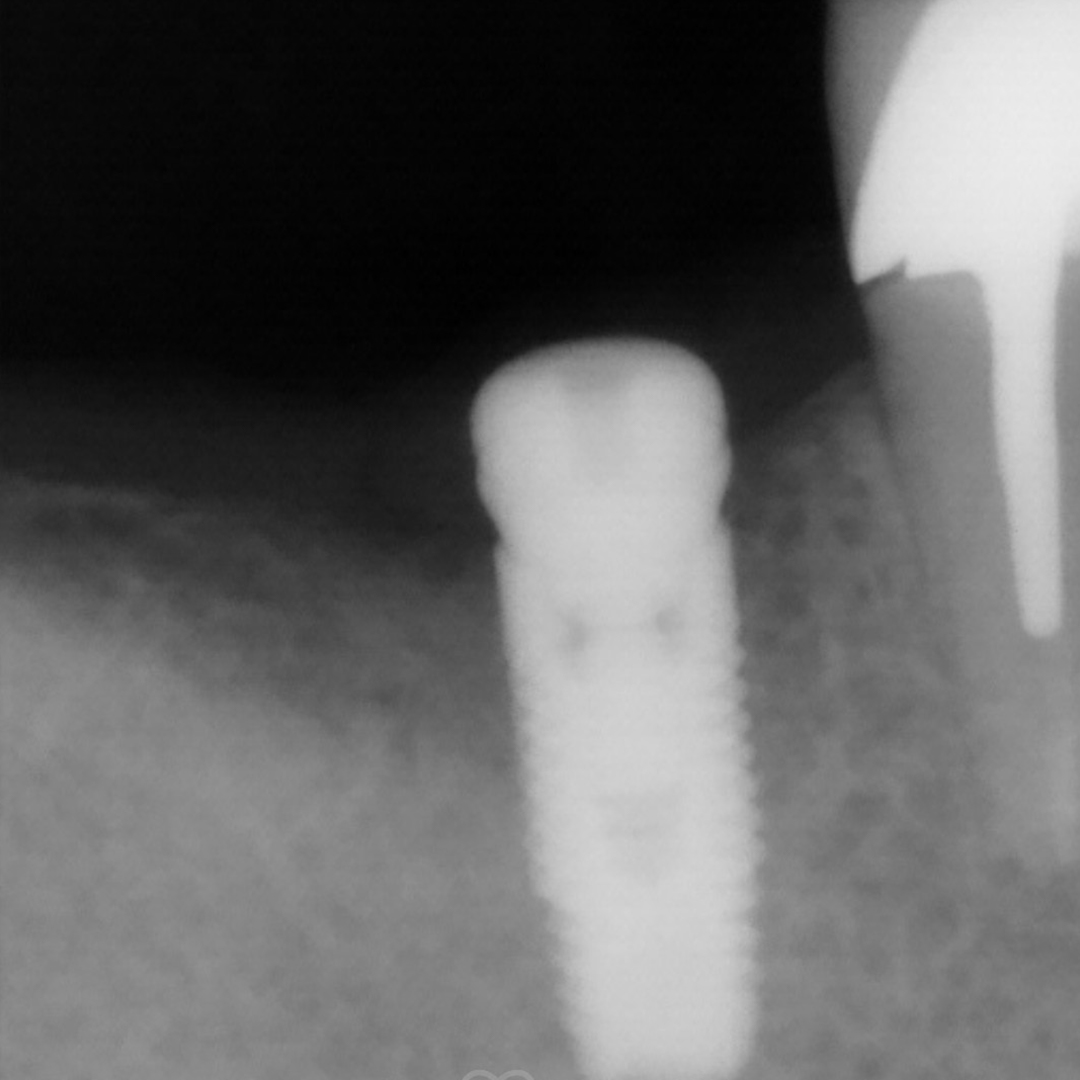

Пациентка обратилась в клинику за установкой зуба, удалённого более года назад, с целью восстановления жевательной функции. Врач стоматолог-терапевт, хирург, имплантолог, ортопед Шандро Евгения Богдановна провела осмотр и анализ компьютерной томографии, после чего принято решение установки импланта Alpha Bio в позицию зуба 4.6.

- установка импланта Alpha Bio;